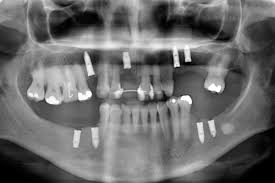

Especialidade que se concentra na colocação de implantes dentários, que são substitutos de raízes dentárias. Os implantodontistas realizam a cirurgia de implante e a restauração protética para substituir dentes ausentes.